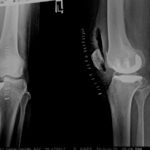

Partial Knee Replacement Surgery

Partial knee replacement is a surgical procedure in which only the damaged portion of the knee joint is replaced, while the healthy parts of the knee are preserved. Unlike total knee replacement, this surgery focuses on the specific area of the knee affected by arthritis, most commonly the inner (medial) compartment.

Because much of the natural knee structure is maintained, partial knee replacement aims to relieve pain while allowing more natural knee movement.